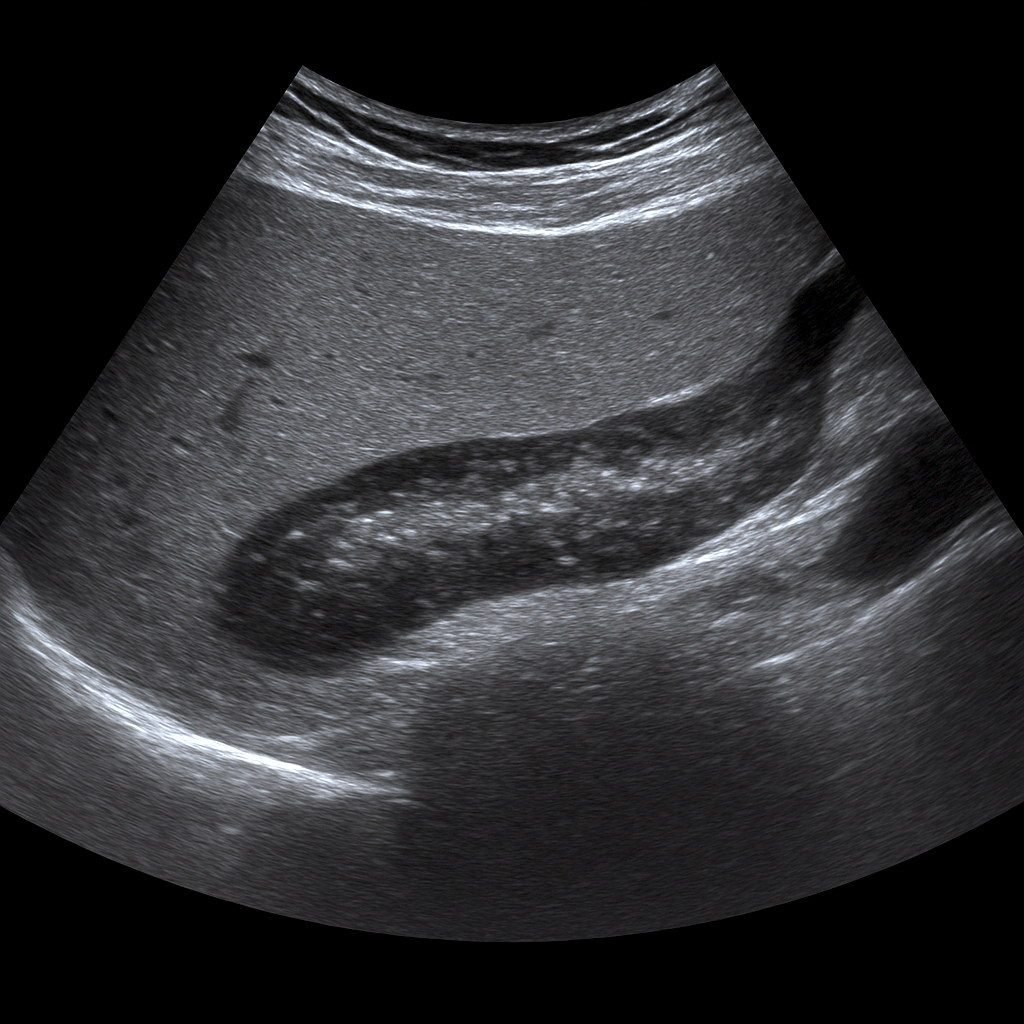

Ultrasound Liver Elastography

Ultrasound

- Ultrasound liver with elastography measures the stiffness of the liver and assesses the degree of fibrosis or cirrhosis.

- Recommended for fatty liver, hepatitis or suspected chronic liver disease.

- Fast, painless and radiation-free method – an alternative to liver biopsy.

- Written opinion and recommendation from a specialist doctor included.